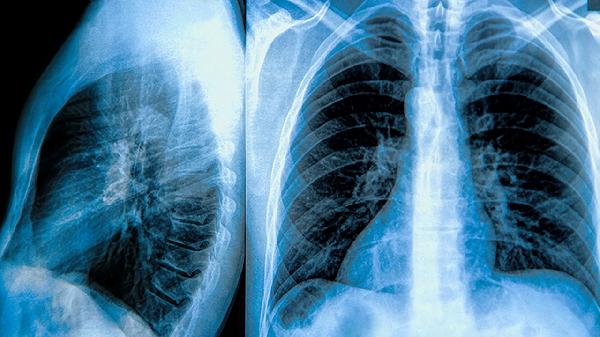

患者常见活动后气促、慢性咳嗽等症状,但无发热、咳脓痰等感染征象。影像学检查可见肺过度充气、肺大泡形成等特征,与传染性肺炎的渗出性病变存在本质区别。